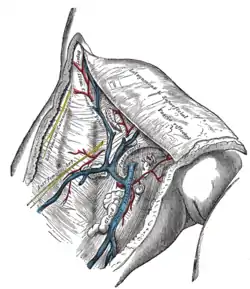

The great saphenous vein and its tributaries at the saphenous opening | |

The cribriform fascia, fascia cribrosa, also Hesselbach's fascia, is the portion of fascia covering the saphenous opening in the thigh. It is perforated by the great saphenous vein and by numerous blood and lymphatic vessels. (A structure in anatomy that is pierced by several small holes is referred to as cribriform from Latin cribrum meaning sieve).[1]

The cribriform fascia has been proposed for use in preventing new vascularization when surgery is performed at the join between the great saphenous vein and the femoral vein.[2]